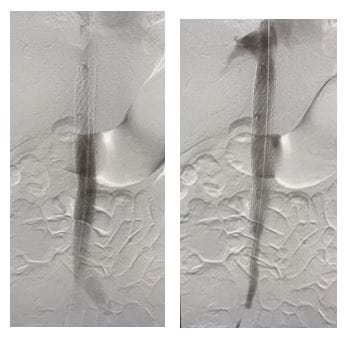

Congenital anomaly during thrombectomy procedureDuring thrombectomy procedure.

Congenital anomaly after stentingAfter stenting.

To address the problem, Dr. Harth performed a staged complete IVC and bilateral iliofemoral thrombectomy and recanalization. In addition, she reconstructed the patient’s congenitally occluded retro-hepatic IVC with IVC stenting.

“Repeat mechanical thrombectomy with a larger device of the residual thrombus allowed us to remove more of the chronic, sub-acute thrombus that we couldn’t remove with suction thrombectomy,” Dr. Harth says. “We then proceeded to dilate up her retro-hepatic IVC which originally started off as an occluded vessel, to a 20 mm diameter with intravascular ultrasound and venographic guidance and ultimately deployed a 20 mm stent.”

“I saw last week in clinic, and she’s doing great,” she says. “At her two week post-visit, she was tolerating her blood thinners and had no leg edema and no symptoms. Follow-up scans show a nice, beautiful open stent. I’m looking forward to seeing her back in four to six weeks. I’m also very excited about our ability to take care of complex patients like this and the support we receive from UH Harrington Heart & Vascular Institute.”